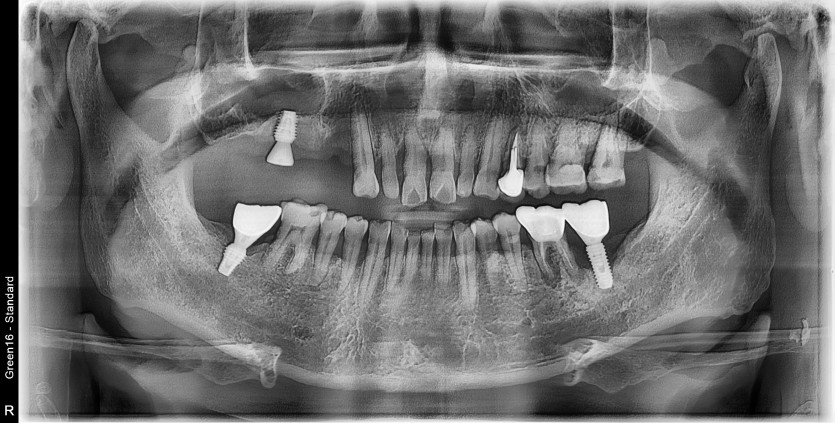

#37 타원 임플란트 제거 후

임플란트 수술+치조골이식술 시행하였습니다.